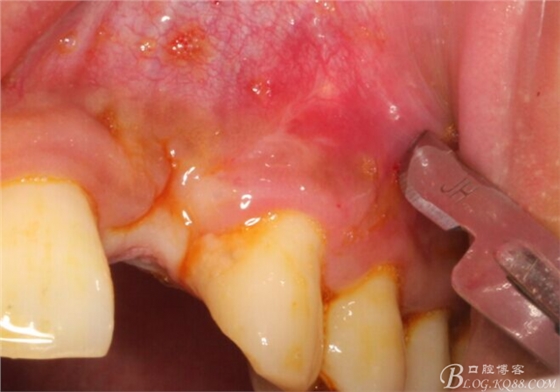

10天拆線一切正常,又過了兩周患者復(fù)診,自述期間無異常。口內(nèi)檢查,真的嚇了一跳,唇側(cè)鼓了個(gè)包,擠壓有白色分泌物溢出,絕對(duì)不是膿液,液體排除后,術(shù)區(qū)觸診空虛,外觀塌陷。這時(shí)候考研大夫的時(shí)刻到了,是先觀察一段時(shí)間再說?還是馬上進(jìn)行處理?我的回答是:馬上處理!如果你沒有及時(shí)處理,而是放患者回家觀察,那么接下來會(huì)發(fā)生如下情況:1.回家后患者家屬及親友會(huì)有很多你可以想象得到的討論;2.患者及家屬會(huì)對(duì)你產(chǎn)生不信任,勢(shì)必會(huì)到其他門診或醫(yī)院檢查,他院大夫會(huì)不會(huì)發(fā)表對(duì)你不利的言論;3甚至?xí)蚁嚓P(guān)法律界人士找你討要說法。

于是我果斷告知患者,手術(shù)失敗了,不能拖延,如不及時(shí)處理,炎癥繼續(xù)發(fā)展會(huì)很快波及鄰牙牙槽骨。患者接受我的建議。切開翻瓣,骨粉及生物膜消失了,骨吸收嚴(yán)重,幸運(yùn)的是,因?yàn)樘幚砑皶r(shí),鄰牙骨支持依然存在。